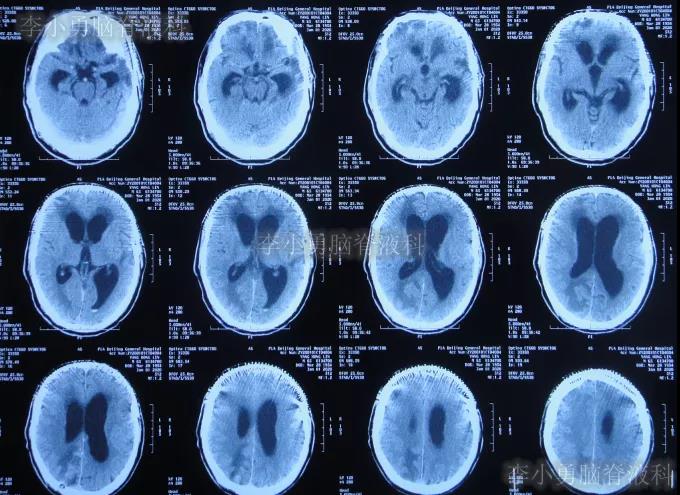

2019年10月20日患者骑电动车在马路上行驶时被大货车撞倒,当时意识清楚,只感到有些头晕,未在意就自行回家,但回家后约3-4小时出现头晕加重,并伴有恶心呕吐的症状,家人急送到当地的河北省邯郸市某医院,查头颅CT示脑出血(图-1);既往病史2015年曾因头部外伤致硬膜下血肿,进行了钻孔引流术。

图-1:2019年10月20日头颅CT